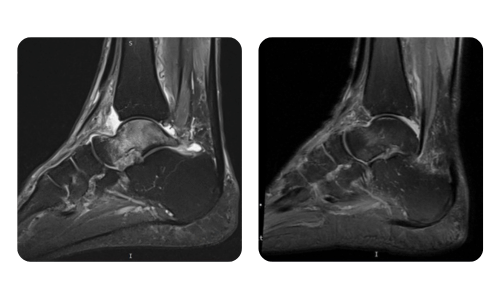

Betegeink előrehaladása, amelyet a hiperbár terápia előtt és után mértünk, tükrözi a kezelés hatékonyságát és pozitív hatását. Fedezze fel a Hyperbarium Oradea hiperbár terápiájának dokumentált eredményeit, amelyek klinikai értékeléseken és objektív adatokon alapulnak, és jelentős javulásokat mutatnak különböző állapotokban.